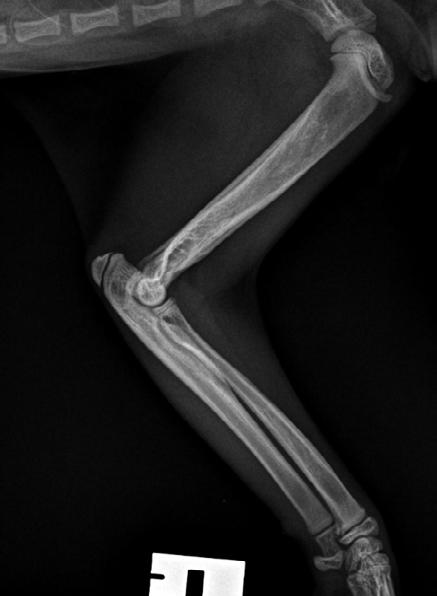

Hotch was booked in for routine castration 4 weeks later with repeat radiographs taken, which already showed improvement (see images). He continued with only oral clindamycin for a further 4 months with regular weight checkups, and dose adjustments as required. We did repeat radiographs under mild sedation a further 2 times to ensure the bone was remodeling as expected (Figure 3 ). Hotch responded almost immediately to the antibiotics and never showed signs of lameness or pain again. He was a robust, busy kitten.

2

Figure 3. Radiograph of the affected leg showing resolving infection and remodeling of the lesion back into a more normal skeletal appearance